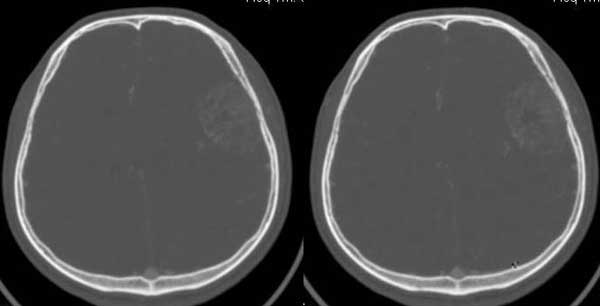

与颅骨广基相连,不均匀强化,脑白质受压,考虑脑外肿瘤,脑膜瘤。

平扫呈低密度,与颅内板接触广泛,脑皮层受压内移,增强明显强化,内示不规则的坏死区,周围脑实质内未见明显水肿.

脑膜瘤.

皮质塌陷,增强比较明显,有一定的占位效应,脑内水肿不显著,脑外病变可肯定,考虑脑膜瘤,但平扫密度较低,颅骨改变也不明显,确实应排除一下脑血管病.

皮质塌陷,增强比较明显,有一定的占位效应,脑内轻度水肿,脑外病变可肯定,考虑脑膜瘤,颅骨内板见局限侵袭改变,警惕恶变

不支持脑膜瘤的地方:每个层面肿块与颅骨内板几乎都呈锐角,相邻颅骨无明显骨质改变。